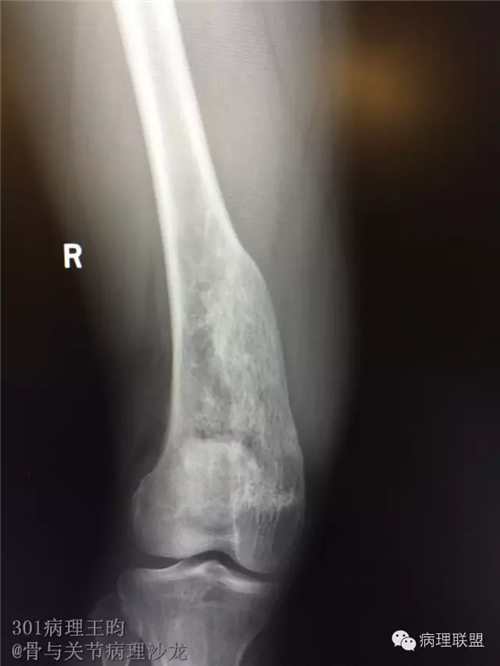

右股骨髓内高分化低级别骨肉瘤or骨纤维异常增殖症(Fibrous Dysplasia)?

男,36岁,活动后疼痛,发现右股骨远端肿瘤。